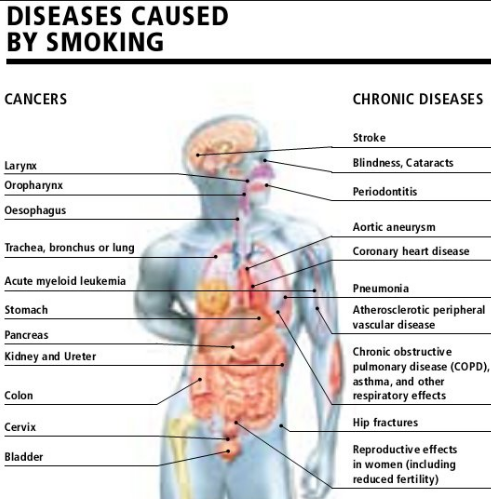

Inilah 16 Penyakit Paling Berbahaya Akibat Merokok Konfrontasi For Justice Truth

Inilah 16 Penyakit Paling Berbahaya Akibat Merokok Konfrontasi For Justice Truth

10 Penyakit Berbahaya Akibat Merokok Apa Saja Itu Yudionline

10 Penyakit Berbahaya Akibat Merokok Apa Saja Itu Yudionline

11 Penyakit Mematikan Akibat Merokok

11 Penyakit Mematikan Akibat Merokok

15 Penyakit Akibat Rokok

15 Penyakit Akibat Rokok